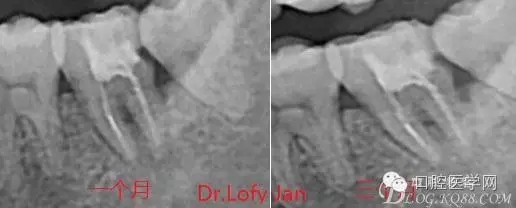

前言:自己做的一些曲面斷層片在未試尖根管治療中的病例整理,發(fā)現(xiàn)問題很多包括自身的,技術(shù)的,還有設(shè)備的問題,予以總結(jié)整理并期待進(jìn)一步提高。

病例分析:曲面斷層片在x線輔助診斷與檢查中目前大多數(shù)文獻(xiàn)和著作都建議只能作為初診拍片檢查手段,不能作為終末疾病的確診與手術(shù)療效的評價指標(biāo),臨床大部分中小型門診都因為設(shè)備不齊全導(dǎo)致信息偏差很大。